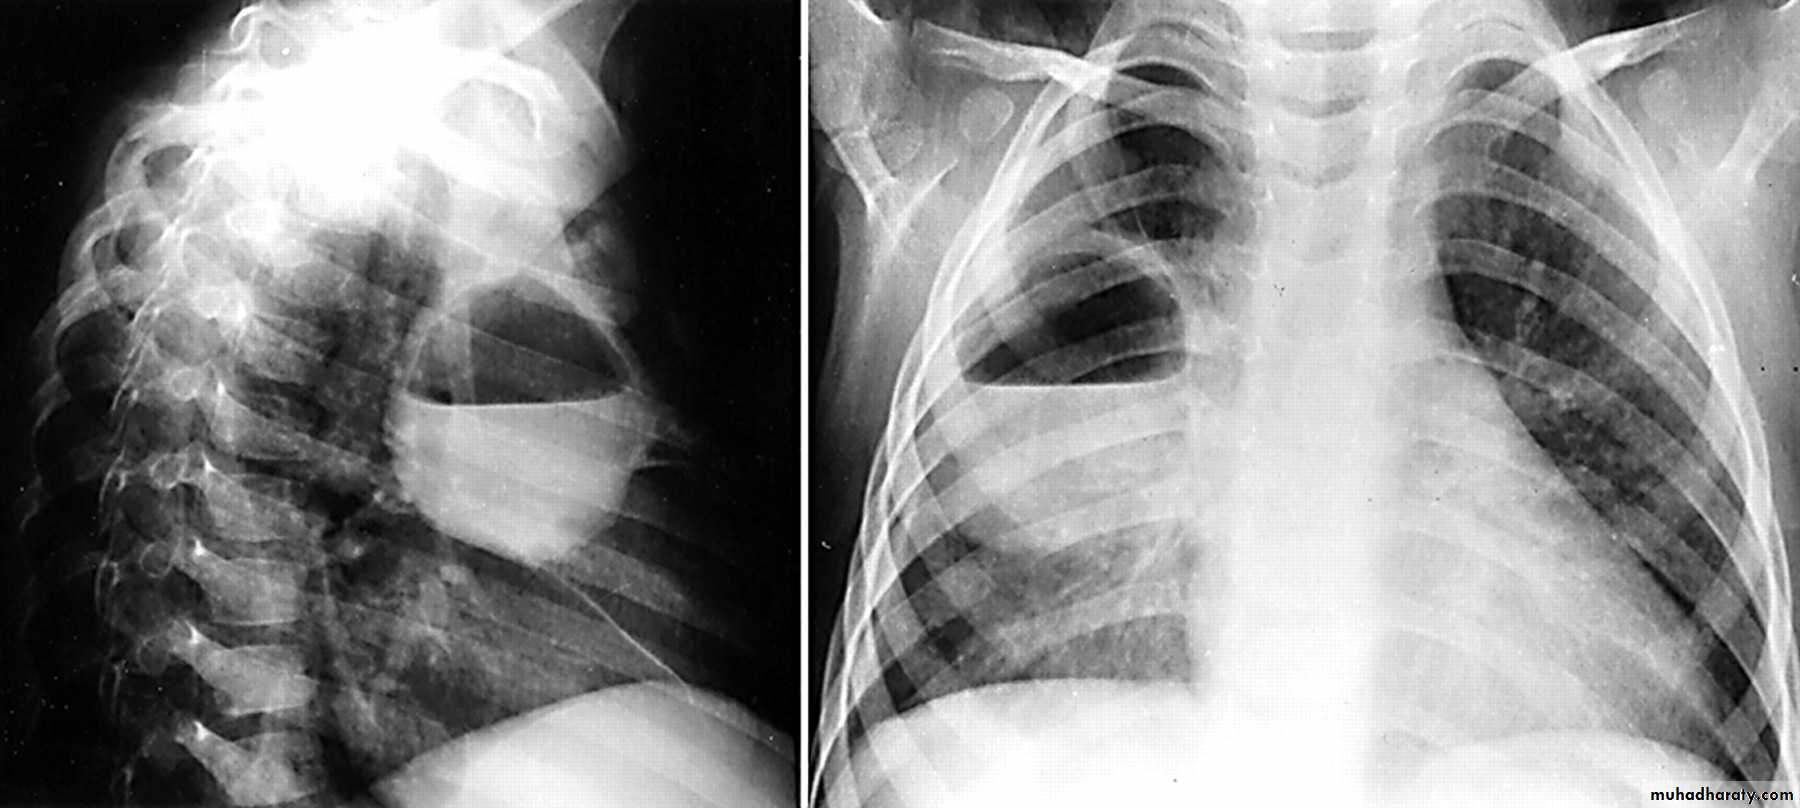

RT UL Consolidation

Klebsiella (Friedlander's) pneumonia: the bulging fissure sign.

bulging fissure sign

RT middle lobe consolidation

RML consolidation

RT lower lobe consolidation

TOTAL LUNG CONSOLIDATION